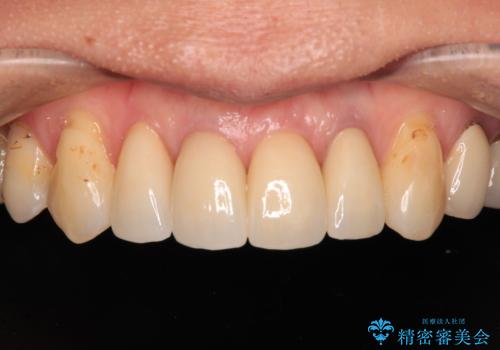

前歯をきれいにやり替えたい

- 他院で治療したラミネートベニアをきれいにやり替えたいと来院された患者様です。

ラミネートベニアの欠けてしまっているところをコンポジットレジンで修復してあり、変色が目立ちます。

また、ラミネートベニアと歯茎の境目も気になります。

根管治療をしている歯もあるため、オールセラミッククラウンにすることとしました。

きれいに仕上がりとても満足されました。